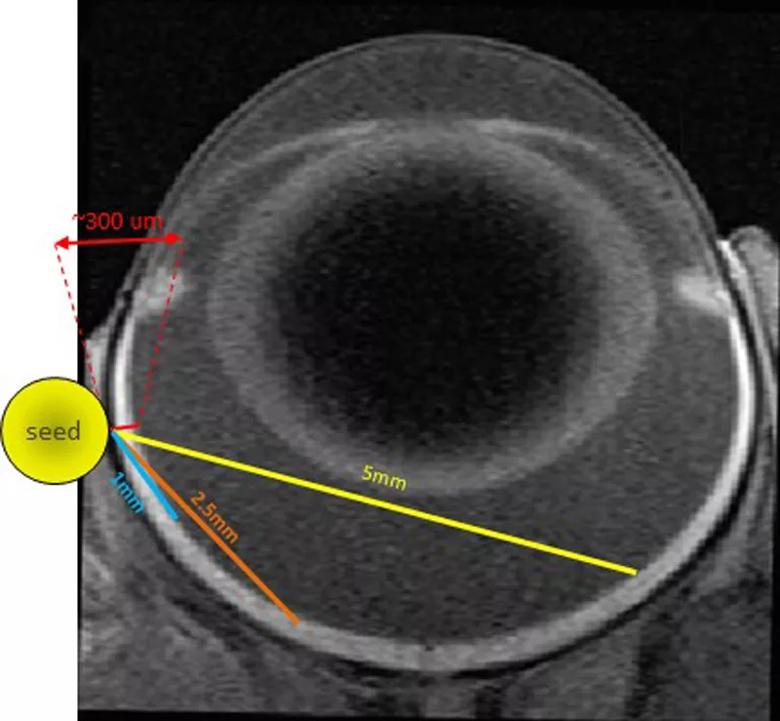

To create our model, a 1 mm by 4 mm radioactive iodine-125 seed was surgically implanted posterior to the limbus of the left eye of Lewis rats (Figure 2). The initial dose of radiation treatment lasted six hours, after which the seed was removed. A total dose of 45 Gy at a distance of 1 mm from the seed was delivered. Escalating dosages of radiation will be administered to find the optimal range.

Image shows positioning of a radioactive iodine seed in the left eye of Lewis rat.

Figure 2. Placement of a 1 mm x 4 mm radioactive Iodine-125 seed surgically implanted posterior to the limbus of the left eye of a Lewis rat.